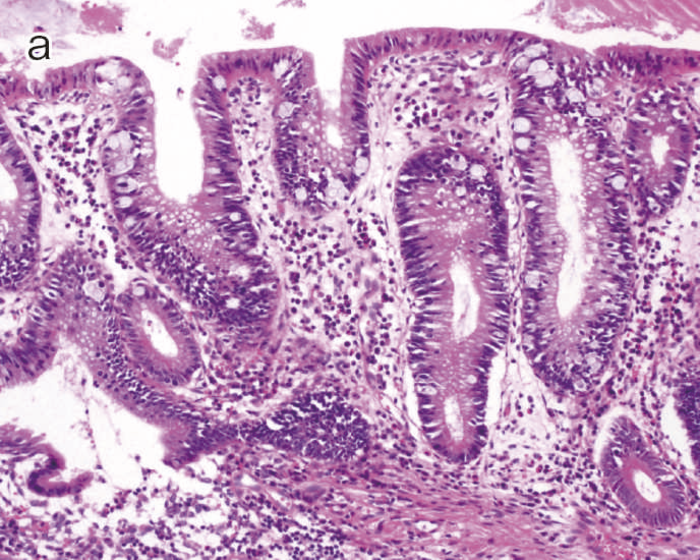

図9 Dysplasiaの代表的な組織像

- LGDの組織像(HE染色):異型腺管では表層への分化傾向が見られる。

- aのp53免疫染色:異型腺管深部側優位にp53蛋白過剰発現が見られる。

このように多彩な像を呈するdysplasiaでは,特に異型度が低い場合に反応性異型との鑑別にしばしば難渋するが,dystrophic goblet cell,endocrine cell hyperplasia,Paneth細胞化生などの特徴的な上皮細胞分化異常を示す特殊な異型上皮の存在が形態学的な鑑別として有用である。また,dysplasiaでは,腫瘍発生早期の段階よりTP53遺伝子異常が起こることが知られている。したがって,上記の形態学的な異常とともに,免疫染色におけるp53蛋白異常発現の有無が反応性異型や散発性腺腫との鑑別において重要となる(TP53遺伝子変異が見られる際には,免疫染色においてp53蛋白過剰発現あるいは完全欠失を示すことが知られている)。これまでに,一般大腸腺腫・癌ではp53蛋白過剰発現はその異型度に相関するのに対し(腺腫で0.8~3.4%,低異型度癌で35.3%,高異型度癌で71.7%),dysplasiaでは低異型度の段階から高頻度(75%)にp53蛋白過剰発現を呈することが報告されている5)。したがって,特に低異型度腫瘍でp53蛋白異常発現パターンを示す場合はdysplasiaの可能性が高く,反応性異型との鑑別において診断的意義が高い。また,表層分化傾向を示すLGDではp53蛋白の過剰発現がある場合でも表層部ではp53蛋白の発現減弱がしばしば観察されるのに対し(unique basal patternと呼ばれる),HGDでは全層性にp53蛋白過剰発現を示すことが多い。Ki-67(増殖マーカー)染色では,dysplasiaでは細胞増殖帯が粘膜深層~中層に位置するが(bottom-up pattern),散発性腺腫では細胞増殖帯が腺管表層~中層に分布することが知られている(top-down pattern)。これらの免疫染色パターンは,dysplasiaと反応性異型や散発性腺腫との鑑別の際に重要な手がかりとなる(図9,図11)(CQ 12,CQ 13)。

表層への分化傾向を示すLGDでは異型腺管深部側優位にp53蛋白過剰発現が見られるのに対し,散発性腺腫ではp53蛋白異常発現は認められない。また,Ki-67(増殖マーカー)染色においては,LGDでは細胞増殖帯が粘膜深層~中層に位置するが(bottom-up pattern),散発性腺腫では細胞増殖帯が腺管表層~中層に分布する(top-down pattern)(CQ 12,CQ 13)。